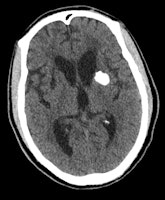

"Knowledge of a history of travel to endemic areas together with biochemical tests, clinical data, and specific imaging findings can often lead to a confident diagnosis," Celzo and colleagues wrote. "Tuberculosis can result in intracranial calcification in 10-20% of cases and is usually located supratentorially in adults and infratentorially in children. Calcified tuberculomas can range in size from about a centimeter to several centimeters and can appear as a 'broken shell' or a dense centrally located lobulated calcification."

Neurocysticercosis is the leading cause of adult-onset seizures in less developed countries, as shown by epidemiological studies, with no consensus on whether the intracranial calcifications are epileptogenic or not, they added. The calcifications represent dead larvae and appear as a dense calcified cyst that sometimes contains a dense eccentric nodule. Lastly, cerebral hydatid disease is an extremely rare cause of intracranial calcification. The lesions are usually single, septated, or multilocular and represent the dead parasite, the authors concluded.